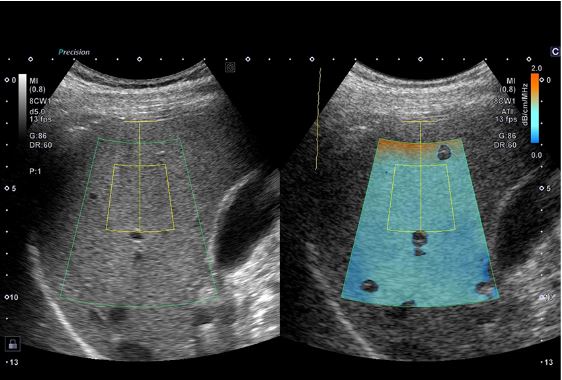

Технологія візуалізації мікропотоків (SMI) відображає кровотоки низької швидкості у нирці.

Технологія Attenuation Imaging (ATI) – кількісна оцінка стеатозу печінки, візуально показує ослаблення ультразвуку в печінці.